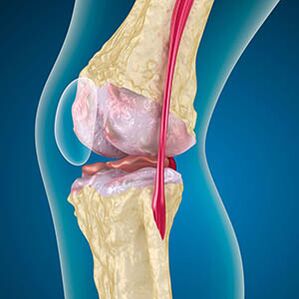

Uz artrozu, hrskavica koja obrubljuje rubove kostiju je abrazija ili potpuno odsutna. Oštećeno tkivo nije izvor boli, jer nema receptore. Upala u obližnjim strukturama uzrokuje karakteristične simptome.

Tijelo nastavlja regeneraciju oštećenih tkiva, ali hrskavica raste neravnomjerno. Kao rezultat toga, formiraju se nepravilnosti koje ozlijeđuju druge elemente zgloba. Priroda osteofita objašnjava se naknadom za glatku zajedničku hrskavicu. Druga verzija ukazuje na rast "Spursa" Povezana je s pokušajem stabilizacije zgloba medijalno ili bočno zbog slabljenja mišića.

Oteklina je uzrokovana ozljedama mekih tkiva, upala tetiva i zglobne vrećice. Izgled topline u koljenu, oticanje ukazuje na akumulaciju upalnog eksudata -Artrozu često prati bursitis, sinoviti, tendinitis.

- sinoviti, pojava ciste pekara ispod koljena;